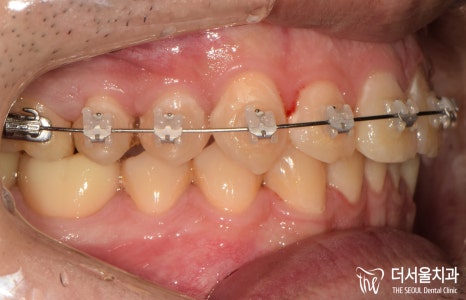

대략 4달이 지났을 때,

조금씩 자리가 생겨나고 있는 것을

찾아볼 수 있습니다.

25번 위치를 보면 처음 내원했을 때보다

조금은 더 열린 것을 볼 수 있죠?

측면으로 봤을 때도

좀 더 치열이 가지런해진 것과,

각자 제 위치를 찾아가는 것이

눈에 띄었습니다.